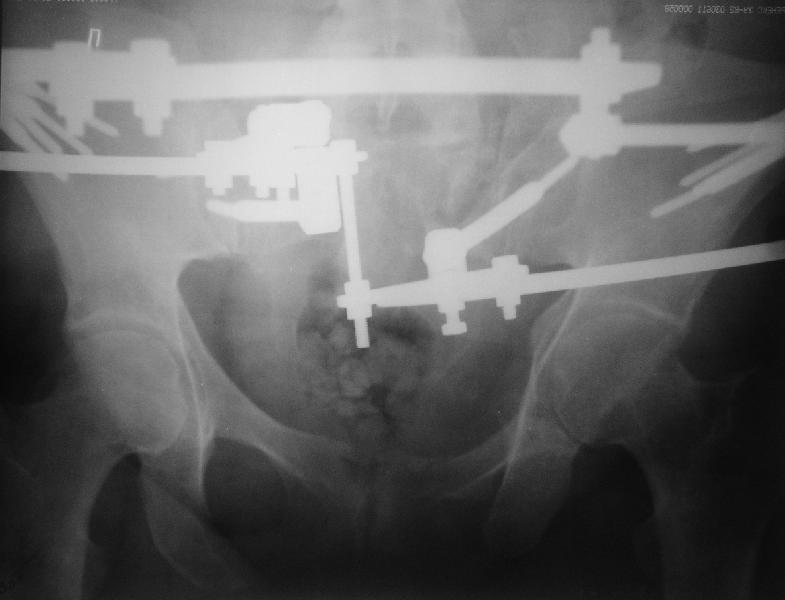

Прооперировали молодую девушку 32 лет спустя 9 мес после травмы.

Имелся стойкий болевой синдром, неопороспособность левой н/конечности, моторные и сенсорные нарушения в левой голени и стопе, патологическая подвижность левой половины таза. Первым этапом закрыто в аппарате исправили деформацию ( в течении 2,5 нед). Вторым закрытое введение илиосакральных винтов в крестец (канюллированные 7,2 мм Chm) + туннелизация зоны псевдоартроза спицама Киршнера, реконструкция передних отделов таза, накостный остеосинтез . Аппарат частично демонтирпован, оставлена "передняя рама" После устранения деформации отмечен регресс неврологической симптоматики, уменьшение болевого синдрома. Интересующие вопросы: 1. Прогноз для сращения псевдоартроза крестца. 2. сроки нагрузки весом левой половины таза. Буду очень признателен за ваши мнения по этому поводу.A female 32 y.o. admitted to our unit 9 months after initial injury with pain, inability to bear weight at the left lower limb, sensor and motor disturbances in the left foot and tibia, with mobility of the left hemipelvis.At first closed reduction was performed by an external fixator within 2,5 weeks. After correction her pain decreased and some neurological progress was achieved. Now two iliosacral screws 7,2 mm were inserted, and anterior lesion was fixed by a plate. External fixator was partially unmounted, only anterior frame left in place.Images attached.How would you evaluate chances of healing of the sacrum with the current position?When would you allow weight-bearing of the left leg?THX in advance.